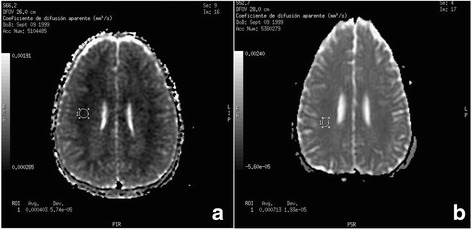

At 48 h, the EEG detected a presence of slow waves but with remarkable bioelectrical improvement, by which sedation was withdrawn. The TCD showed an increase in average speeds (180–190 cm/s) in all the territories with predominance in the left hemisphere, compatible with moderate-severe vasospasm. Thus treatment was started with intravenous nimodipine. The patient maintained BIS values <50 in the following 12 h, later waking up and being subsequently extubated after 72 h of PICU admission (GCS 13–14). The subsequent MRI showed hyperintensity white matter signals in FLAIR and T2 sequences, in relation to base metabolic leucoencephalopathy (Fig. 1a), but also indicated new sources which in the diffusion-weighted imaging, showed a reduced apparent diffusion coefficient (ADC) indicative of cytotoxic edema (Fig. 2a).

Fig. 2.

Diffusion-Weighted Imaging in MRI, comparing the ADC map, at 72 h (Image a) and after 8 months (Image b). It may be observed that the circular region of interest to determine the ADC value in both images: with values of: 0,4 × 10−3 mm2/s at 72 h (restricted diffusion), whilst after eight months the value was 0.7 × 10−3 mm2/s (normal ADC map value)

On the 8th day neurological examination was normal as that of EEG and TCD testing, withdrawing treatment with nimodipine. Once again, when the patient was discharged we recommended continued treatment with L-carnitine. The MRI performed at 8 months indicated a normalization of ADC, but with the presence of specific areas with increased signal in T2 and FLAIR sequences indicative of definitive residual injury in the periventricular brain parenchyma as well as those areas of previous demyelination (Figs. 1b and 2b). Currently, the patient maintains clinical normality.

Characteristically, the neuroimaging studies carried out on these patients show diffuse cerebral white matter hypodensity on CT scan and hyperintensity on T2 weighted MRI studies [3, 5]. However, there is less information on the findings of the neuroimaging tests during an acute episode. In the MRI, we detected that the cerebral edema was of the cytotoxic type with the restriction of diffusion in the ADC map. In it, the swelling cell produces a decrease in the extracellular space and a decrease in the molecular diffusion that is quantified and that in our patient was diminished in the initial study, normalizing in the test carried out 8 months later. This finding has not been previously described.